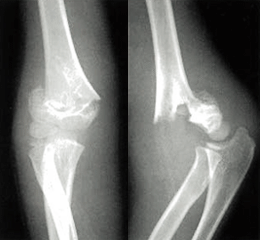

「上腕骨顆上骨折」

X線(レントゲン)検査で、診断を行います。

※日本手外科学会「手外科シリーズ 19」から画像を引用しております。